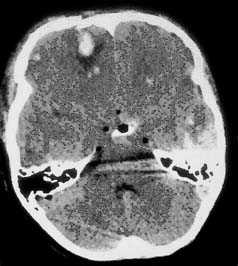

Компьютерная томография при травматическом повреждении головного мозга

Применение компьютерной томографии в нейротравматологии существенно изменило представление о возможностях диагностики различных черепно-мозговых повреждений. КТ является в настоящий момент «золотым стандартом» - наиболее информативным методом обследования больных с черепно-мозговыми травмами и позволяет в самые короткие сроки судить о механизмах возникновения поражения мозга, его характере, распространенности, выраженности отека и дислокации мозга, а также динамике этих изменений.

КТ позволяет последовательно изучить мягкие ткани головы, кости черепа, вещество мозга, эпидуральные, субдуральные, субарахноидальные пространства, цистерны основания и желудочки мозга:

- выявить переломы свода и основания черепа (с чувствительностью, намного превышающей традиционную рентгенографию) ,

- выявить наличие внутричерепной гематомы (её характер, локализацию, размеры),

- выявить наличие очага ушиба головного мозга (его локализацию, размеры, характер, наличие геморрагического компонента),

- определить степень сдавления или дислокации головного мозга объемным процессом,

- выявить наличие диффузного или перифокального отека и его степени,

- выявить субарахноидальное кровоизлияние,

- выявить внутрижелудочковую гематому,

- выявить наличие пневмоцефалии.

Визуализация минимальных количеств излившейся свежей крови, уверенная дифференциация ее от других внеклеточных жидкостей, слежение за динамикой отека и набухания головного мозга, некроза и восстановления его структур с одновременным распознаванием переломов костей черепа, особенно его основания, составляют преимущества КТ перед магнитно-резонансной томографией.